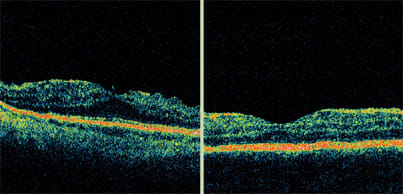

This patient received five treatments with pegaptanib sodium (Macugen), but active disease remained. Following treatment with bevacizumab (Avastin), vision and appearance of the retinal anatomy on OCT improved, but some fluid still remained. Treatment with ranibizumab (Lucentis) further improved vision and led to resolution of the retinal fluid. The patient is now being followed with OCT as the sole imaging modality.

The Stratus OCT continued to detect AMD disease activity after the patient was treated with PDT and bevacizumab. After one injection of ranibizumab, OCT showed a normal retinal appearance and vision improved to 20/30.